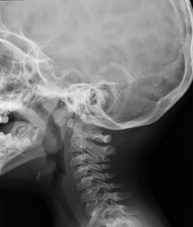

- RX Cráneo

Técnica mediante la cual, utilizando rayos X, se obtienen imágenes del cráneo para su estudio. Indicaciones: traumatismo, cierre precoz de suturas craneales. - RX Senos Paranasales

Técnica mediante la cual, utilizando rayos X, se obtienen imágenes de los senos paranasales para su estudio. Indicaciones: dificultad respiratoria nasal, tos crónica, cefalea, mucosidad. - RX ATM (Articulación Temporo-Mandibular)

Técnica mediante la cual, utilizando rayos X, se obtienen imágenes de la articulación temporo-mandibular para su estudio. Indicaciones: traumatismo, dolor al masticar, ruido al masticar, limitación en la apertura bucal. - RX Cavum

Técnica mediante la cual, utilizando rayos X, se obtienen imágenes del cavum para su estudio. Indicaciones: dificultad respiratoria, anginas de repetición en lactantes y niños. - RX Columna cervical

Técnica mediante la cual, utilizando rayos X, se obtienen imágenes de la columna cervical para su estudio. Indicaciones: traumatismo, contractura cervical, dolor articular. - RX Huesos propios nasales

Técnica mediante la cual, utilizando rayos X, se obtienen imágenes del cuello para su estudio. Indicaciones: estudio de bultos o nódulos. - RX Charnela

Técnica mediante la cual, utilizando rayos X, se obtienen imágenes de la charnela o de la base del cráneo para su estudio. Indicaciones: estudio de malformaciones congénitas.

- Cervical spine X-ray

This technique uses X-ray rendered imaging for examining the cervical spine. Indicated for: trauma, cervical pain.

- Cavum X-ray

This technique uses X-ray rendered imaging for examining the cavum. Indicated for: respiratory distress, regurgitation, recurrent otitis.